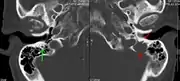

Medical imaging

The diagnostic examination of a person with suspected multiple myeloma typically includes a skeletal survey. This is a series of X-rays of the skull, axial skeleton, and proximal long bones. Myeloma activity sometimes appears as "lytic lesions" (with local disappearance of normal bone due to resorption) or as "punched-out lesions" on the skull X-ray ("raindrop skull"). Lesions may also be sclerotic, which is seen as radiodense.[70] Overall, the radiodensity of myeloma is between −30 and 120 Hounsfield units (HU).[71] Magnetic resonance imaging is more sensitive than simple X-rays in the detection of lytic lesions, and may supersede a skeletal survey, especially when vertebral disease is suspected. Occasionally, a CT scan is performed to measure the size of soft-tissue plasmacytomas. Nuclear Medicine Bone scans are typically not of any additional value in the workup of people with myeloma (no new bone formation; lytic lesions not well visualized on nuclear bone scan).